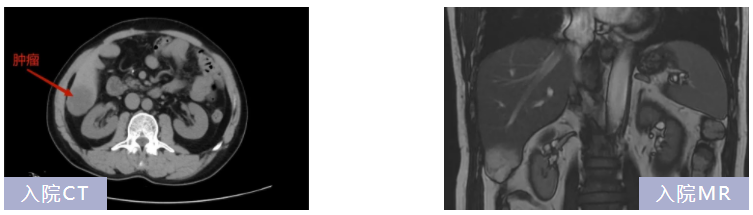

張大爺(化名)2年前曾因“升結(jié)腸癌”在北大醫(yī)療淄博醫(yī)院進行手術(shù),手術(shù)非常順利。近期在醫(yī)院復查時,發(fā)現(xiàn)新發(fā)肝腫瘤。肝膽外科主任王龍華接診了張大爺,結(jié)合其病史及輔助檢查,初步診斷為結(jié)腸癌肝轉(zhuǎn)移瘤(單發(fā))。

考慮肝臟血供豐富,肝臟腫瘤切除術(shù)中容易出血,手術(shù)風險大,許多基層醫(yī)生將其視為手術(shù)禁區(qū)。王主任立即組織肝膽外科專家開展病例討論,研究手術(shù)方案,同時邀請北醫(yī)三院、肝膽外科專家蔣斌教授會診,圍繞術(shù)前診斷、手術(shù)方式、手術(shù)風險及術(shù)前準備進行充分評估,最終實施腹腔鏡肝腫瘤切除術(shù)。